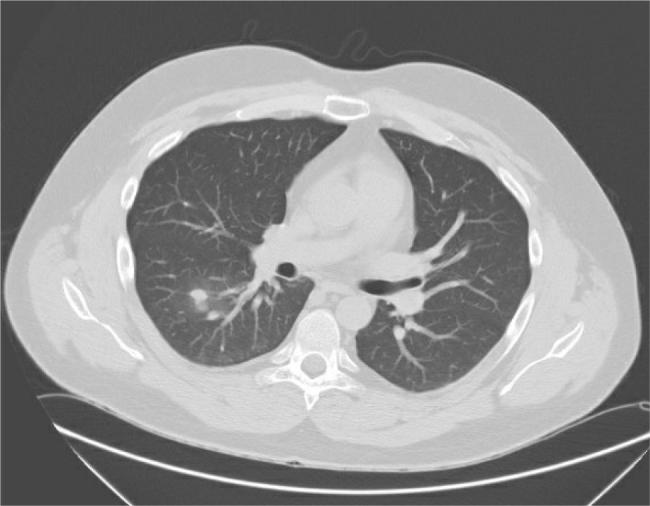

We report the case of a 29-year-old male who presented with new-onset diabetes mellitus, resistant hypertension and significant weight gain. Physical examination revealed features consistent with Cushing's syndrome. Biochemical evaluation confirmed ACTH-dependent hypercortisolism with an elevated plasma ACTH level, and a lack of suppression on high-dose dexamethasone testing; imaging identified a suspicious pulmonary nodule. Bronchoscopic biopsy revealed no malignancy, however cultures grew species. The patient denied any respiratory symptoms or environmental exposure. Initial antibiotic therapy with ciprofloxacin and rifampin was started. Follow-up imaging showed rapid enlargement of the pulmonary mass, prompting surgical resection. Histopathology revealed malakoplakia, and repeat cultures again yielded Antibiotics were adjusted to azithromycin and rifampin, and the patient was started on ketoconazole to manage hypercortisolism.

我们报告一例29岁男性病例,该患者出现新发糖尿病、难治性高血压和显著体重增加。体格检查发现符合库欣综合征的特征。生化评估证实为促肾上腺皮质激素(ACTH)依赖性皮质醇增多症,血浆ACTH水平升高,且高剂量地塞米松试验无抑制反应;影像学检查发现一个可疑的肺结节。支气管镜活检未发现恶性肿瘤,但培养物中生长出[具体物种名称]。患者否认有任何呼吸道症状或环境暴露史。开始使用环丙沙星和利福平进行初始抗生素治疗。随访影像学检查显示肺部肿块迅速增大,促使进行手术切除。组织病理学显示为软斑病,再次培养又分离出[具体物种名称]。抗生素调整为阿奇霉素和利福平,并开始让患者服用酮康唑来控制皮质醇增多症。